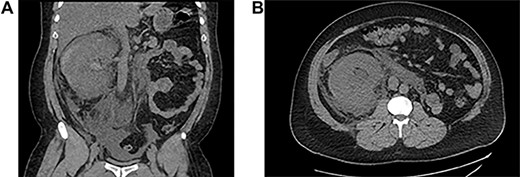

He underwent ureteroscopy and removal of ureteric stent which was inserted 3 weeks ago for an upper ureteric radiolucent stone in another hospital. The patient did not report passing the stone but ureteroscopy was negative. During his recovery after ureteroscopy and stent removal the patient developed right flank pain on Day 1 postoperative and presented to initial hospital, and was discharged from the emergency department on oral analgesics. On the third day he presented to our hospital with anuria and shortness of breath and generalized edema. His laboratory finding showed creatinine level at presentation was 735. Computed tomography (CT) abdomen without contrast showed a subcapsular hematoma with mild hydronephrosis (Fig 1). The patient was taken for percutaneous drainage using 8 Fr nephrostomy tube which drained hematouric urine with clots of 1.5 L (Fig. 2). Post drainage the patient had good urine output and the creatinine level dropped to 492. He was monitored for possible postobstructive diuresis which was anticipated and managed. He recovered his renal functions and creatinine level went back to normal levels with good urine output. On the third day the nephrostomy tube was clamped, and the patient was voiding freely with no flank pain or leak. The nephrostomy tube was removed, and he was discharged. A follow-up CT after 1 month showed complete resolution of the hematoma and the renal profile was normal.

Antegrade pyelogram post drainage and insertion of nephrostomy tube.